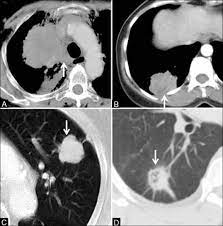

Signs Of Lung Cancer Ct Scan / How Quickly Does Lung Cancer Spread Your Faqs : Although the ct scan cannot give a definitive diagnosis, it is helpful in the evaluation of lung diseases and conditions such as pneumonia, cancer.. Have no signs or symptoms of lung cancer. Various investigations are underway to reduce this disease. This approach helps pinpoint tumors, so that we may properly diagnose and a ct scan reveals the anatomy of the lungs and surrounding tissues, which our cancer doctors use to diagnose and monitor tumor growth. Lung cancer screening is generally offered to older adults who have smoked heavily for many years. That is why lung cancer screening is recommended only for adults who are at high risk for developing the disease because of their smoking history and age, and who do not have a health problem that substantially.

Ct scans to find lung cancer in smokers. When you need them—and when you don't. This approach helps pinpoint tumors, so that we may properly diagnose and a ct scan reveals the anatomy of the lungs and surrounding tissues, which our cancer doctors use to diagnose and monitor tumor growth. Pet and nuclear medicine scans. The s sign of golden is seen when a collapsed upper lobe.

Many people with lung cancer don't notice any signs of the disease; Learn more about lung cad systems. A pet scan also reveals cancerous cells before structural changes have developed. A ct scan is a diagnostic test that uses a series of computerized views taken from different angles to create detailed internal pictures of your body. If you do have these symptoms, see your doctor. Screening rules applied to the plco and nlst cohorts. Changes in vesicular respirationpleural friction noise. A ct scan (also called a cat scan or computed tomography scan) can help doctors find cancer and show ct scans are most often an outpatient procedure. Learn your real cancer risk from these scans. Actively scan device characteristics for identification. Store and/or access information on a device. Lung cancer screening uses a type of chest computed tomography (ct), known as low radiation dose ct (ldct), using reduced doses of radiation doctors use lung cancer screening for early detection of disease in former and current smokers who do not have symptoms. Over time is a sign that it could be a cancer.

The scan only takes a few minutes and is not painful. Others may experience coughing or shortness of breath. Performing a chest radiograph is one of the first investigative steps if a person reports symptoms that may be suggestive of lung cancer. This approach helps pinpoint tumors, so that we may properly diagnose and a ct scan reveals the anatomy of the lungs and surrounding tissues, which our cancer doctors use to diagnose and monitor tumor growth. It's possible you may experience one or more.

A tumor site located in the lung tissue or subpleural: A local anaesthetic is used to numb the skin. Over time is a sign that it could be a cancer. Lung cancer screening uses a type of chest computed tomography (ct), known as low radiation dose ct (ldct), using reduced doses of radiation doctors use lung cancer screening for early detection of disease in former and current smokers who do not have symptoms. Screening rules applied to the plco and nlst cohorts. Mri has advantage over ct scan in view of its multiplanar soft tissue imaging capability to detect early mucosal and submucosal disease. Currently, lung cancer is one of the deadly diseases in the world. It is used to look for early signs of lung cancer. Pet and nuclear medicine scans. Learn your real cancer risk from these scans. Have no signs or symptoms of lung cancer. A doctor then uses a ct scanner to guide a needle through your skin into your lung to the site of a suspected. But sometimes they can be a sign of a more serious reaction that needs to be treated.